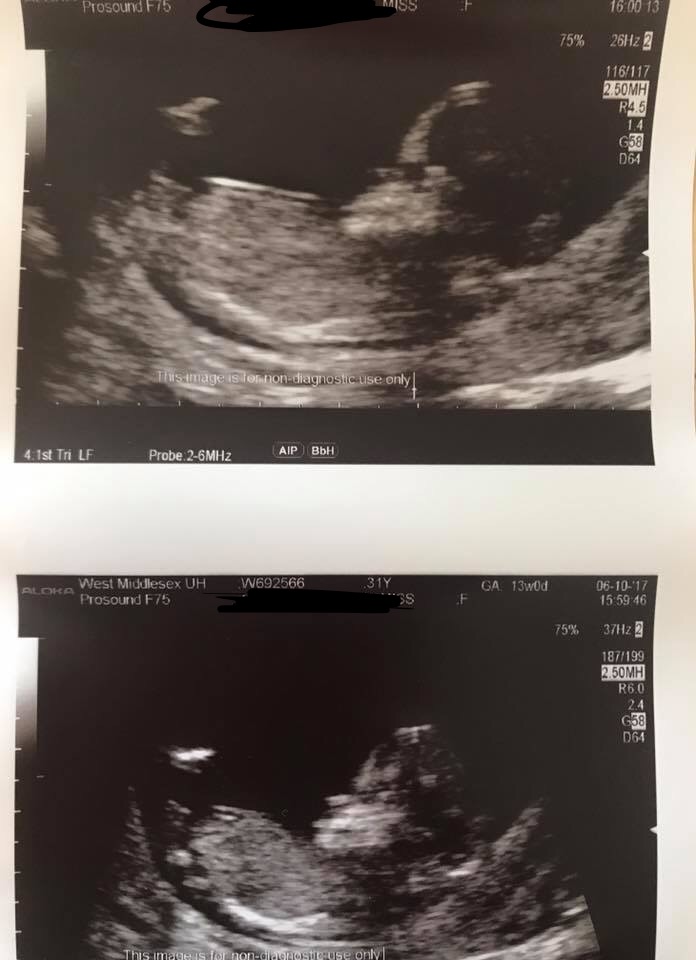

Boy. It looks like stacking on the nub in the first pic.